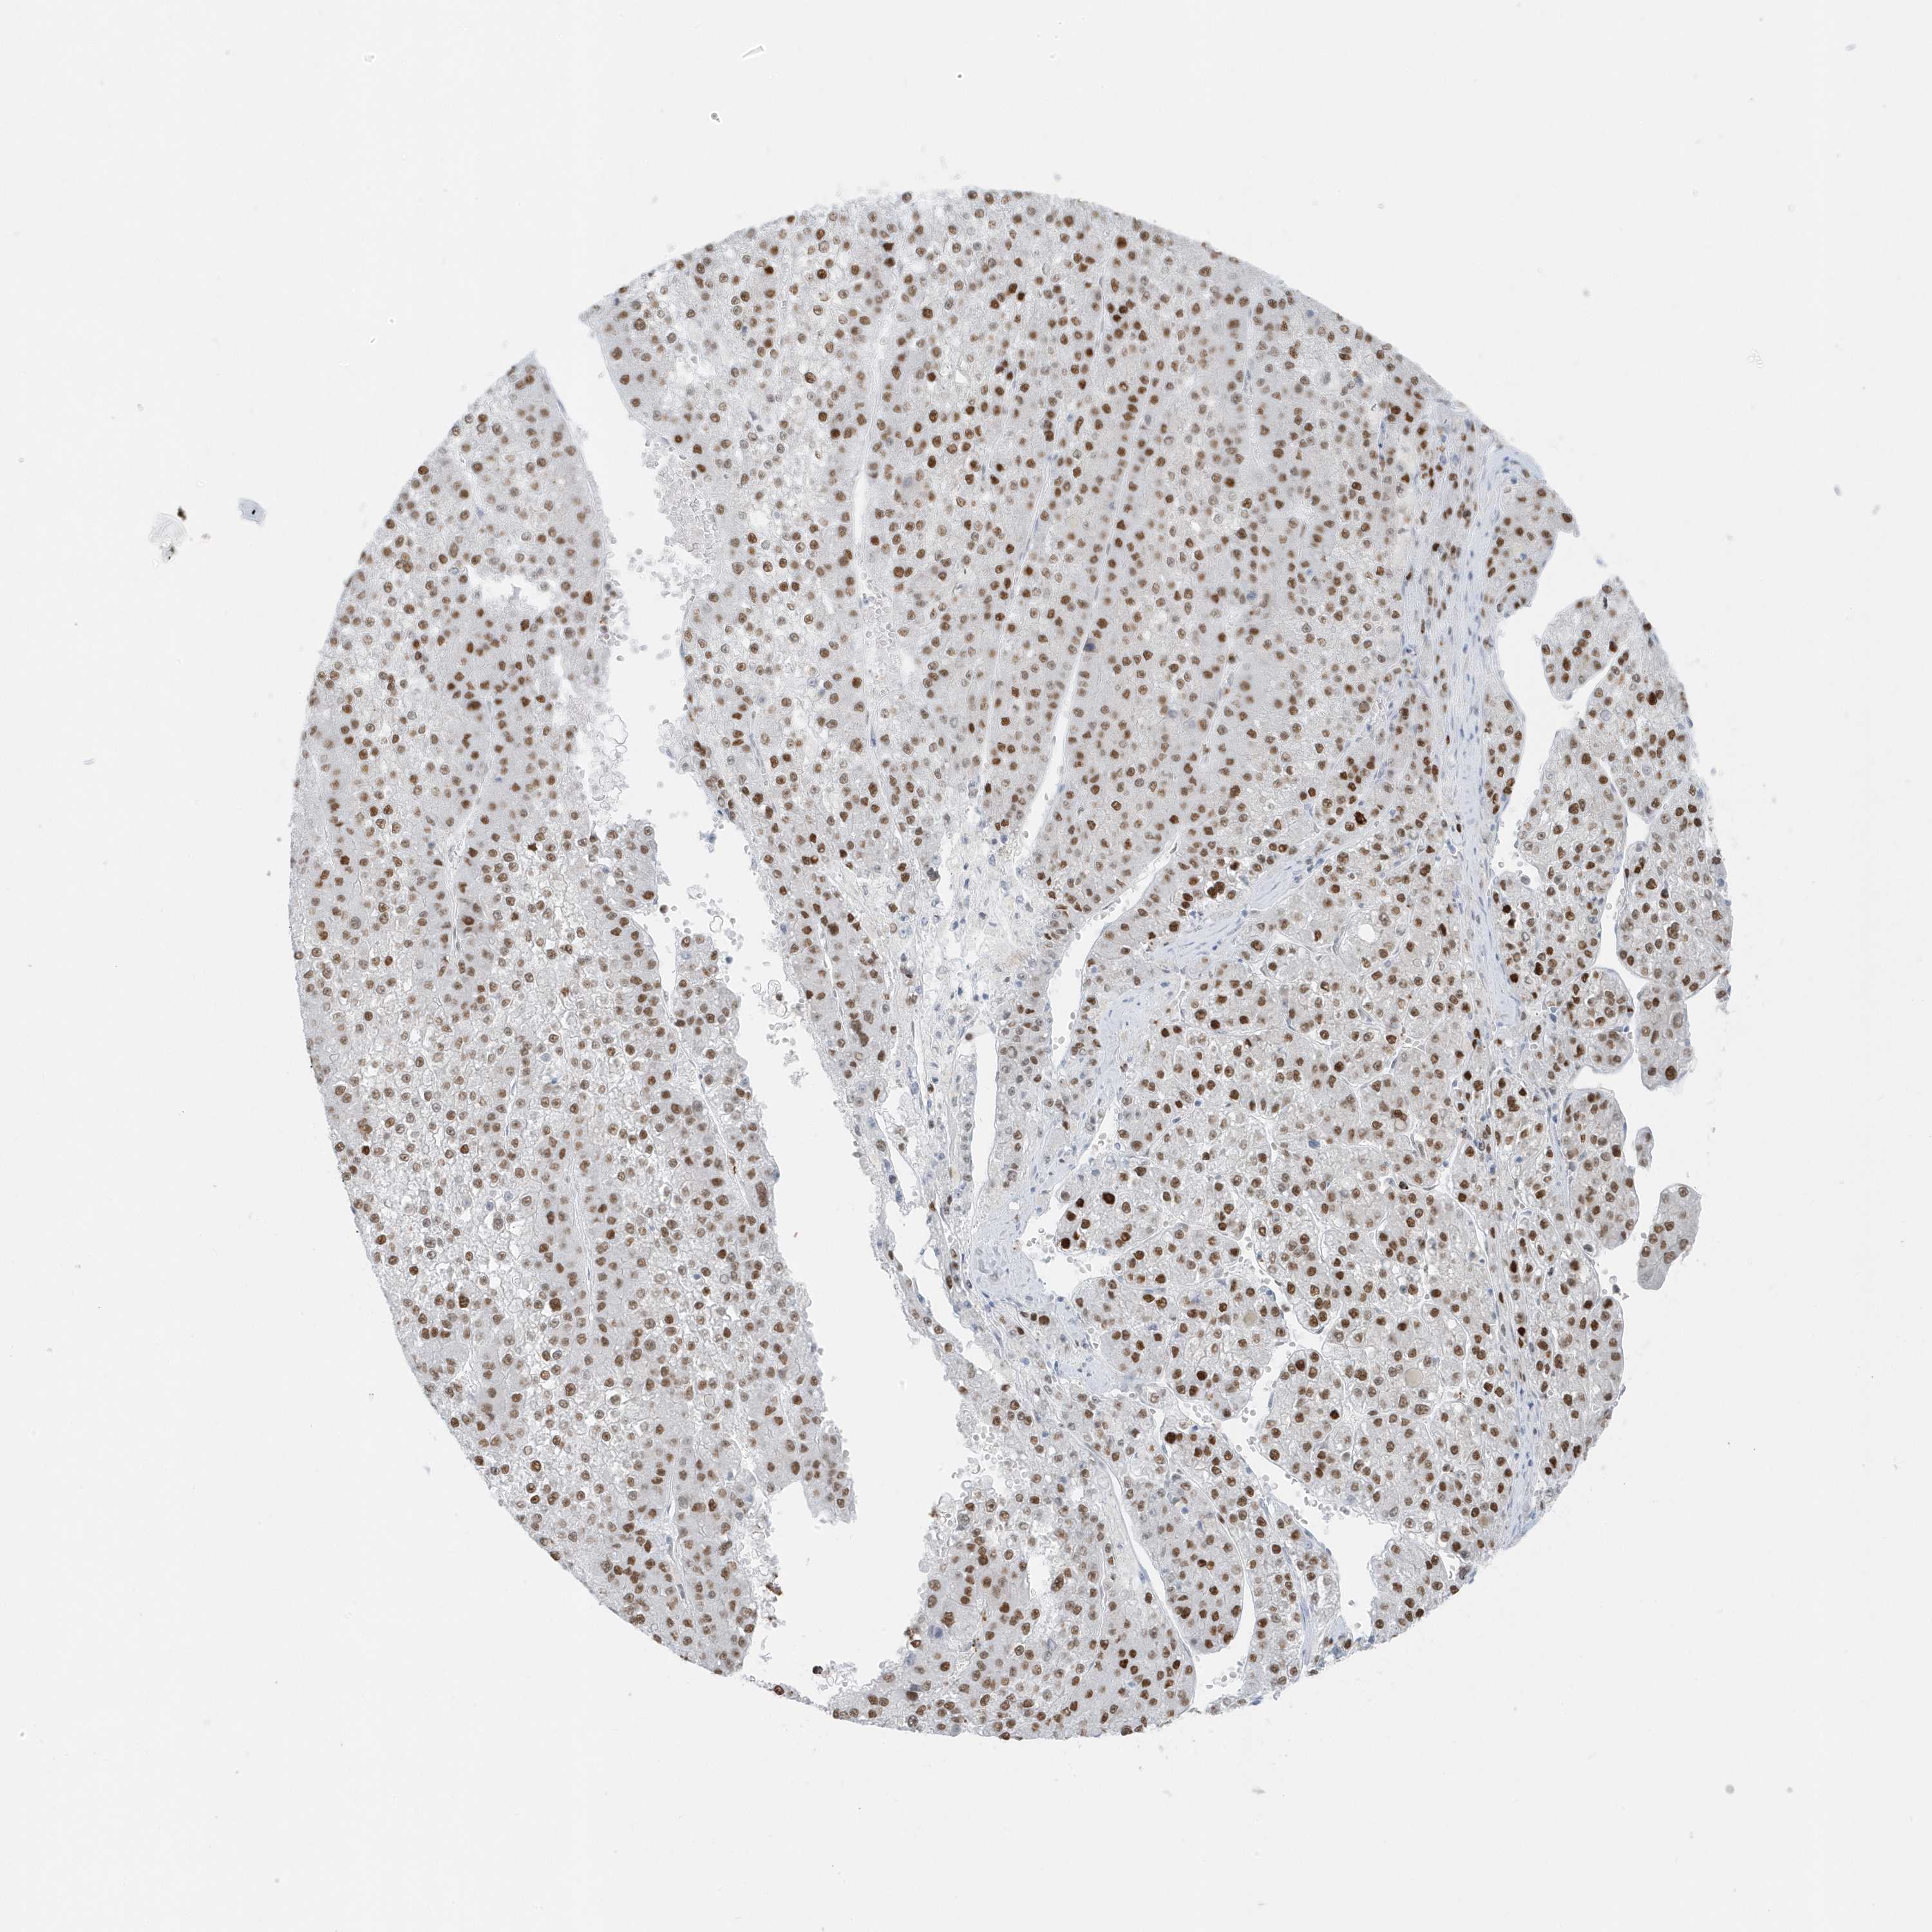

LIVER CANCER - Protein expressioni

A mouse-over function shows sample information and annotation data. Click on an image to view it in a full screen mode. Samples can be filtered based on level of antibody staining by selecting one or several of the following categories: high, medium, low and not detected. The assay and annotation is described here.

Note that samples used for immunohistochemistry by the Human Protein Atlas do not correspond to samples in the TCGA dataset.

Antibody stainingi

Antibody staining in the annotated cell types in the current human tissue is reported as not detected, low, medium, or high, based on conventional immunohistochemistry profiling in selected tissues. This score is based on the combination of the staining intensity and fraction of stained cells.

Each image is clickable and will lead to virtual microscopy that enables deeper exploration of all samples and also displays staining intensity scores, fraction scores and subcellular localization as well as patient and tissue information for each sample.

Antibody HPA029085

Staining

High

Medium

Low

Not detected

Intensity

Strong

Moderate

Weak

Negative

Quantity

>75%

75%-25%

<25%

None

Location

Nuclear

Cytoplasmic/membranous

Cytoplasmic/membranous,nuclear

Carcinoma, Hepatocellular, NOS